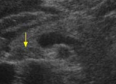

Identify this image.

Normal variant of uncinate process in which it contains less fat than remainder of pancreas